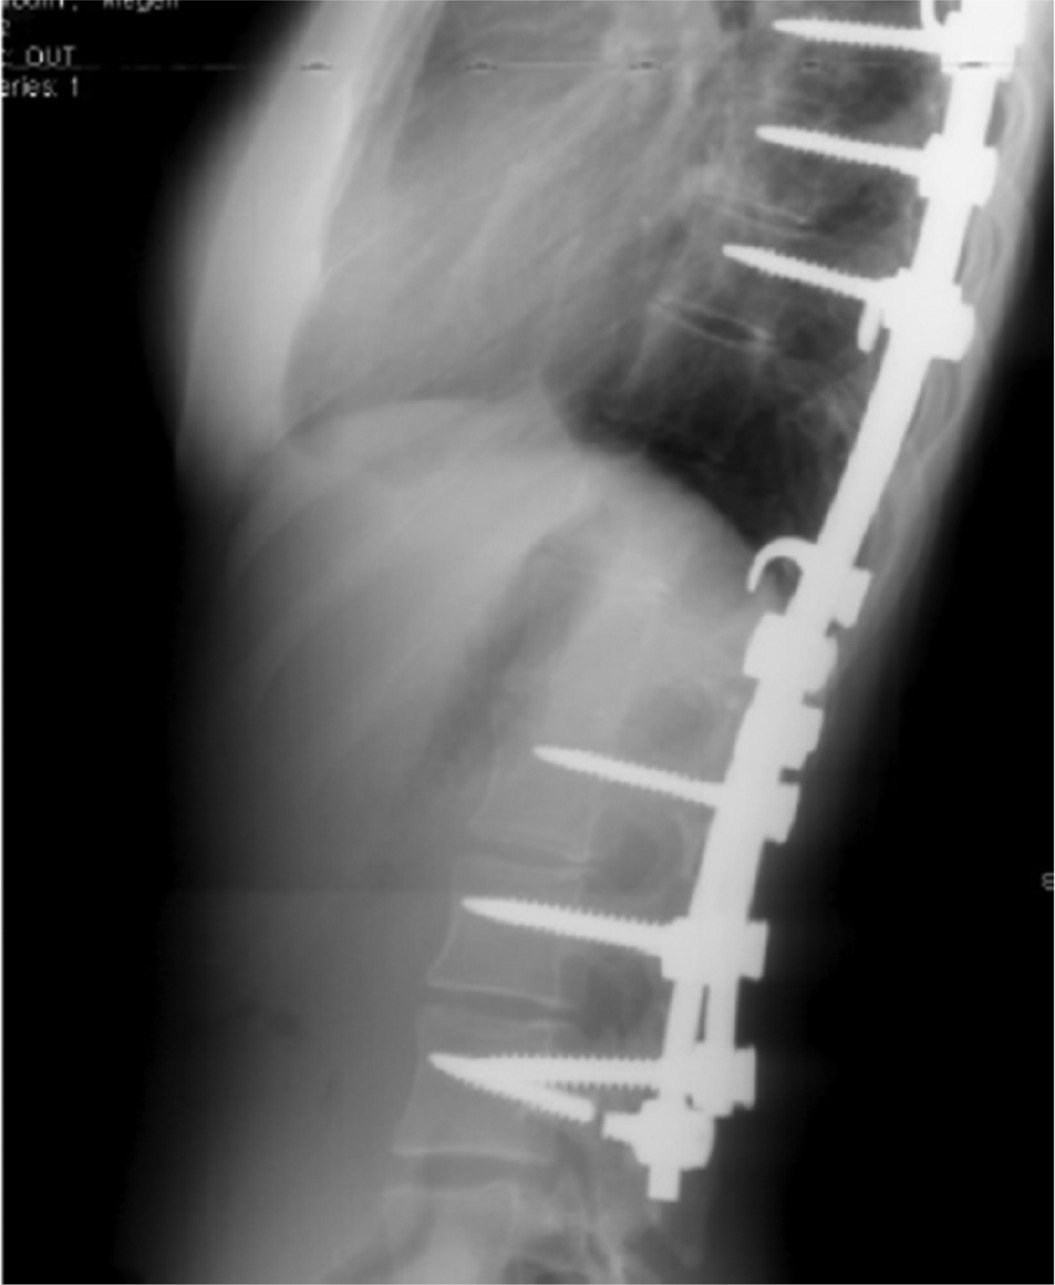

Mechanical low back pain is a diagnosis of exclusion, so making this diagnosis requires ruling out other causes of back pain, especially those associated with risk of significant complications. In the postoperative population, plain films are important to rule out other sources of pain, especially implant-related problems (Figure 1), progressive deformity, or adjacent degeneration.

Figure 1. Pedicle screw fracture with low back pain may indicate pseudarthrosis.